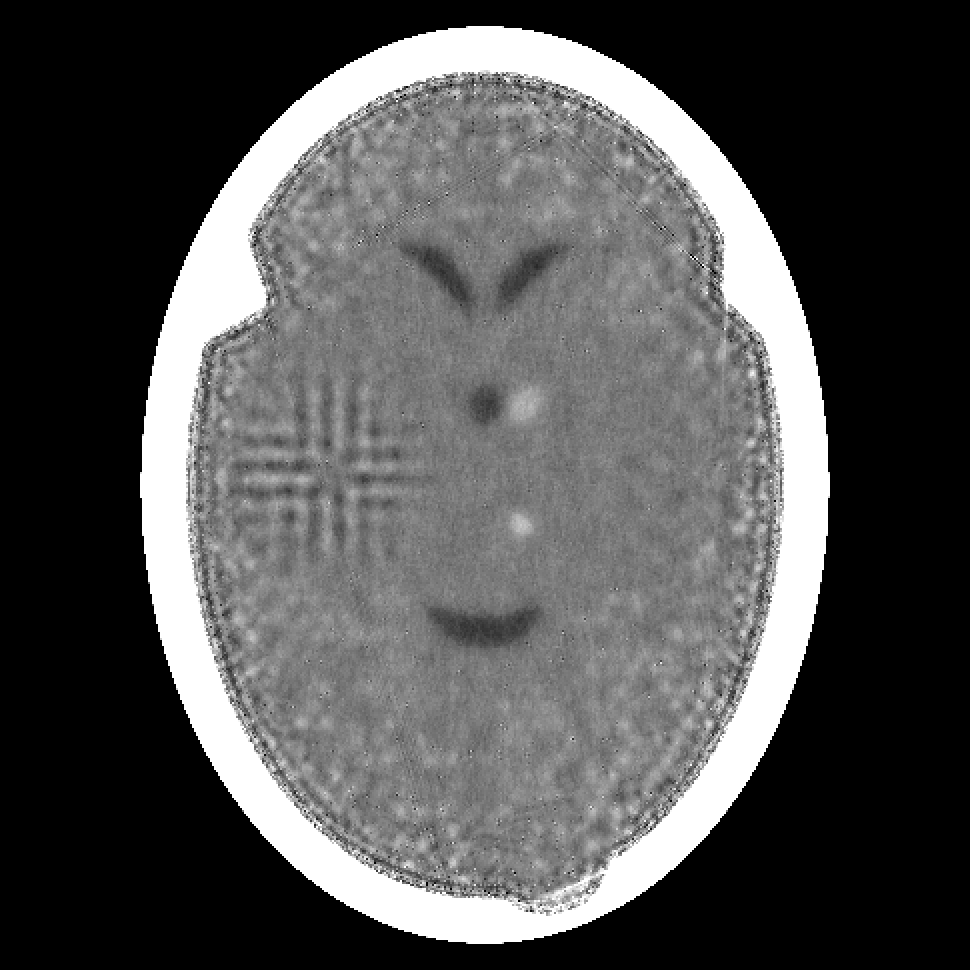

Figure 2: Reconstructions from 180 projections by (a) filtered back-projection, (b) the algorithm ART, (c) TV-Based Superiorized Version of ART, and (d) Shearlet-Based Superiorized Version of ART.

For this anecdotal experiment we use three different numbers of views (i.e., projections): 180, 360, and 720. We emphasize that, in the currently-described anecdotal experiment, there is only one phantom (which provides the ground truth); random generation of local inhomogeneities and of tumor locations is done only once and the same arrangement of local inhomogeneities and of tumor locations is used when generating the projection data for the three different numbers of views.

We present the visual results of the reconstructions produced by these algorithms when using 180, 360, and 720 projections in Figures 2, 3, and 4, respectively. We now give our impressions based on these visual results.

In the case of 360 projections, the resulting images still show that none of the algorithms provides clear visualization of the small tumors; although they are somewhat visible in the images produced by filtered back-projection and by ART. The Shearlet-Based Superiorized Version of ART still shows high-frequency artifacts, albeit less pronounced than in the case of 180 projections. TV-superiorized ART produces an image in which the features, especially the small tumors, are smoothed out, but the larger features within the brain are clearly identifiable.